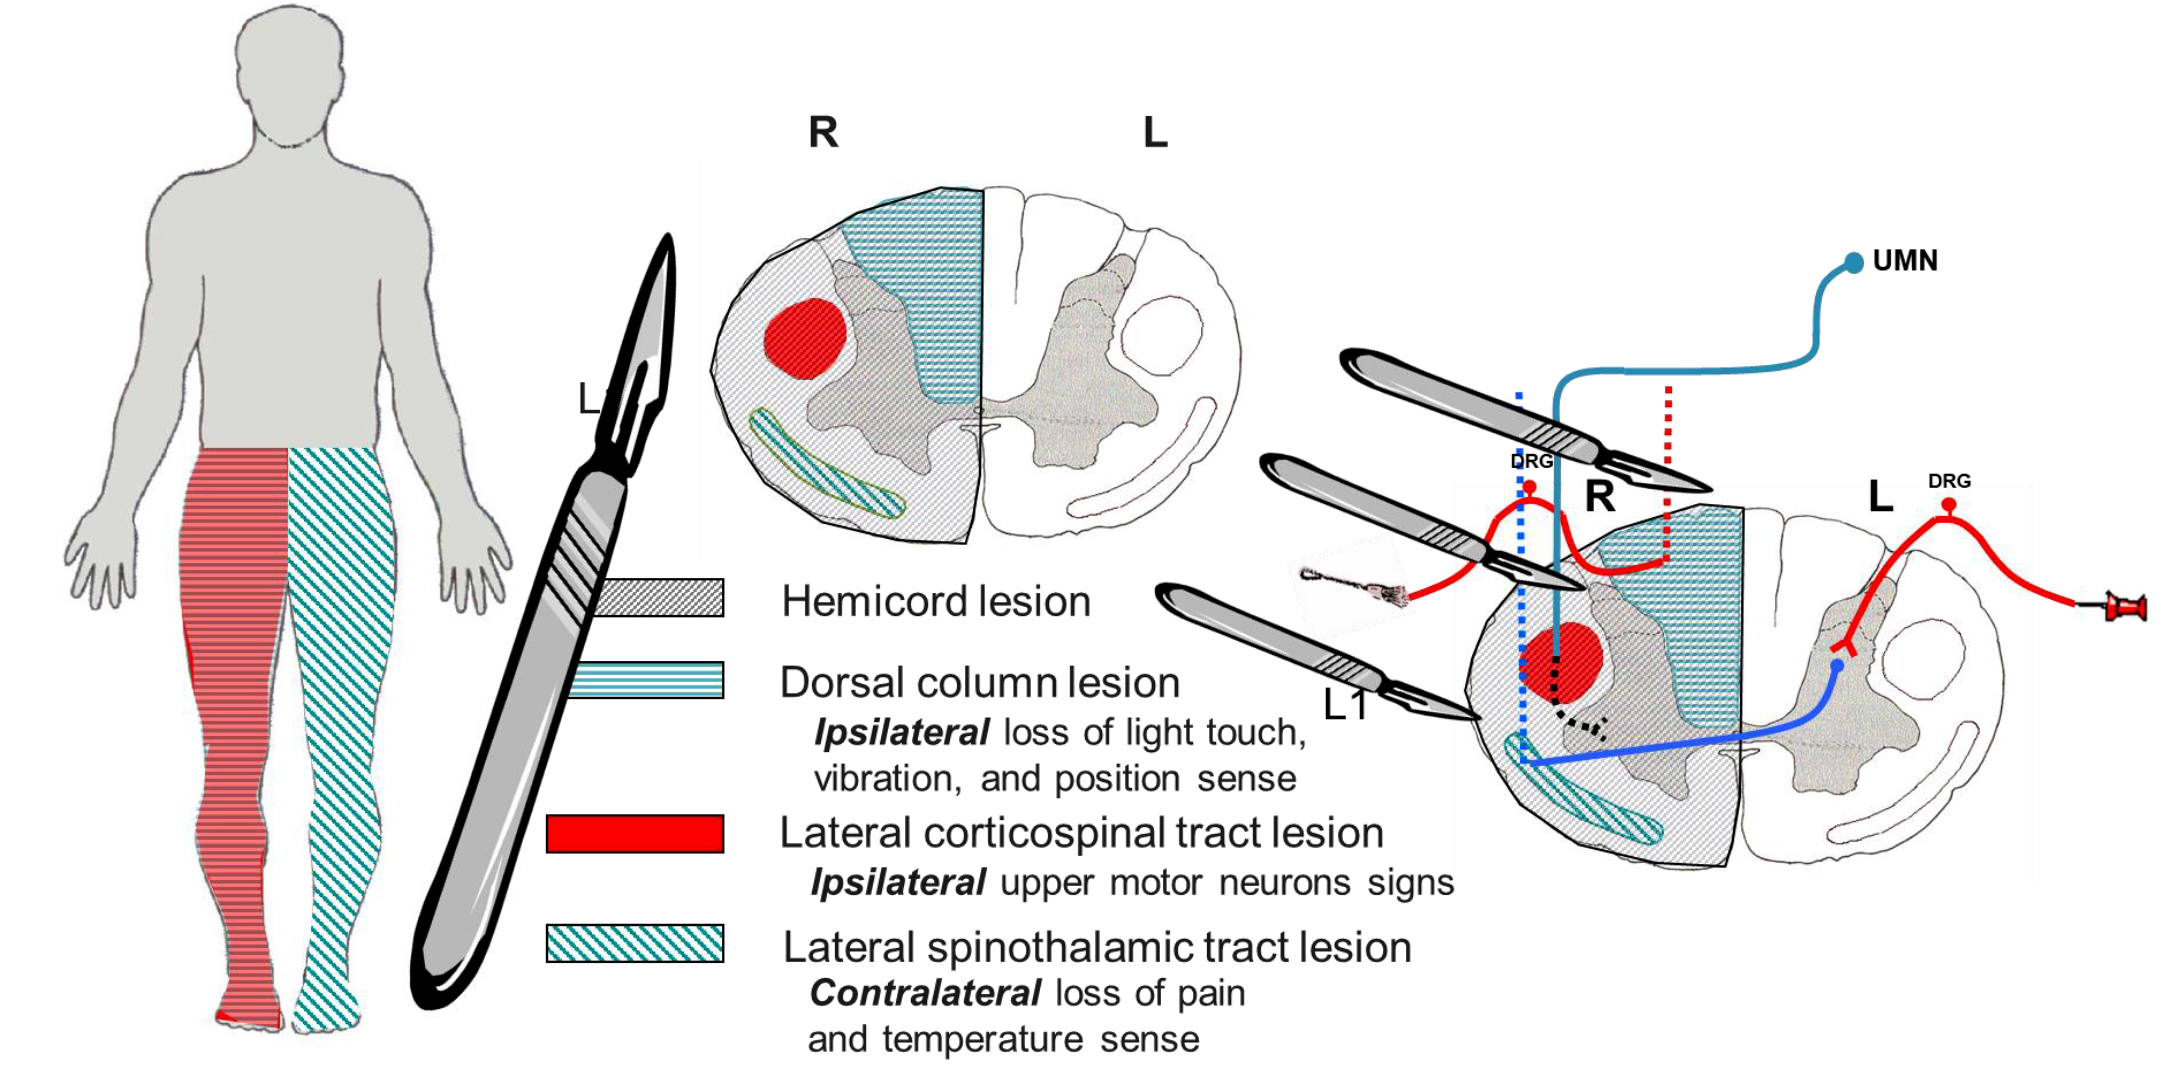

Brown squart syndrome

Lesion results in:

Dorsal column lesion – Ipsilateral loss of light touch, vibration, and position sense Lateral corticospinal tract lesion – Ipsilateral upper motor neurons signs Lateral spinothalamic tract lesion – Contralateral loss of pain and temperature sense